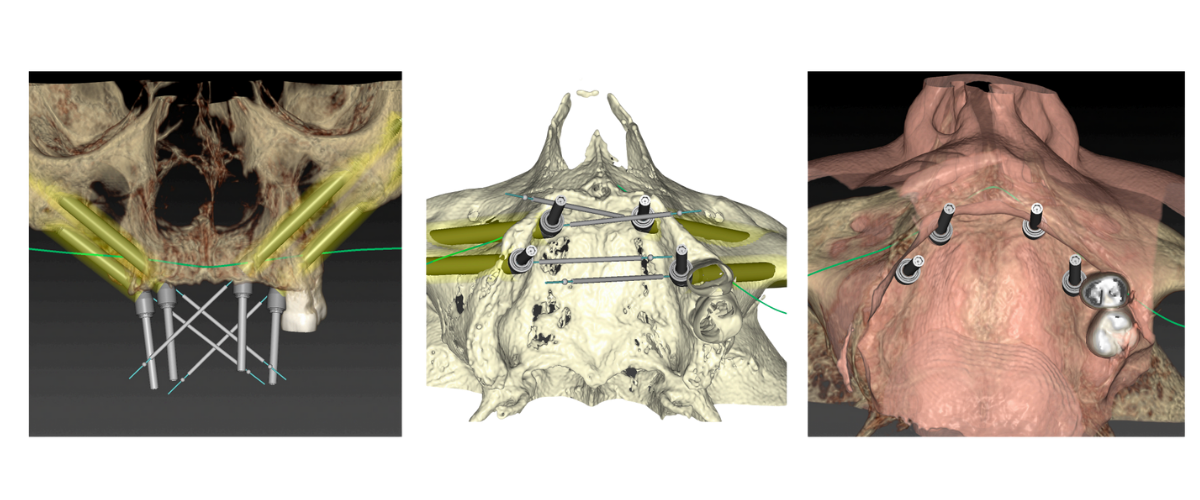

Realizamos CT helicoidal y con FOV ampliado, imprescindible para el diseño de las guías.

Planificamos cuidadosamente la colocación de los implantes teniendo en cuenta, tanto la anatomía maxilofacial como la de la futura prótesis

Colocamos los implantes cigomáticos según las guías quirúrgicas que hemos diseñado en planificación 3D.

Planificación 3D y confección de férulas quirúrgicas para abordaje guiado.